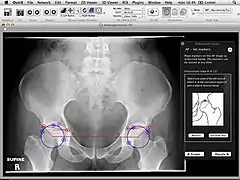

Orthopaedic Studio is an application designed to help orthopaedic specialists perform several common quantitative hip examinations that are based on standard x-ray images.

The application is implemented as a plugin for the medical image viewer OsiriX and thereby only runs on Mac OS X.

Orthopaedic Studio evaluates four different types of hip radiographs (standing anteroposterior, Von Rosen, false profile and frog). On such images a number of standardized angles, offsets and ratios can be measured, including:[1]